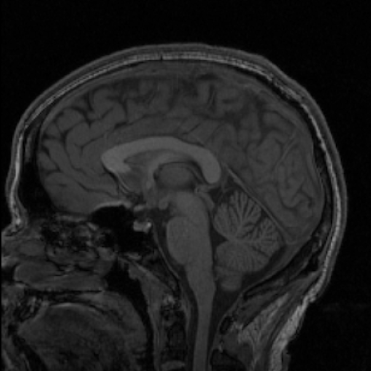

I used the Maker Hub 3D printers to print out a 1:1 scale model of my own brain after getting an MRI this past summer. Additionally, I printed the brains of about 26 participants in a neuroimaging study I was a research assistant for during Summer 2018. 3D printing helped facilitate my research by providing our 9-13 year old participants with scale models or their individual brains, both providing them with a physical reminder of the study and allowing them to feel involved.